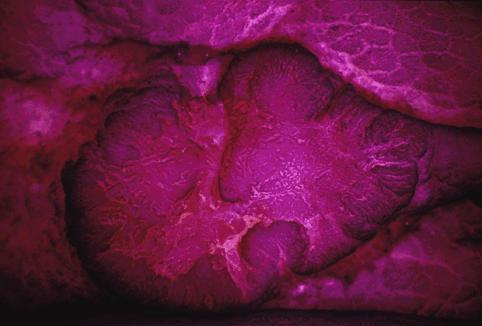

Criteria of Hist.ClassificationMalignant epithelial tumor/Adenocarcinoma

LocationLarge intestine(Colon)/Sigmoid colon

Technique, MethodMacro.

Macroscopic TypesType 0/IIa (IIa+IIc) Superficial elevated and depressed type

Size15 - 19

Depth of Tumor Invasionsubmucosa